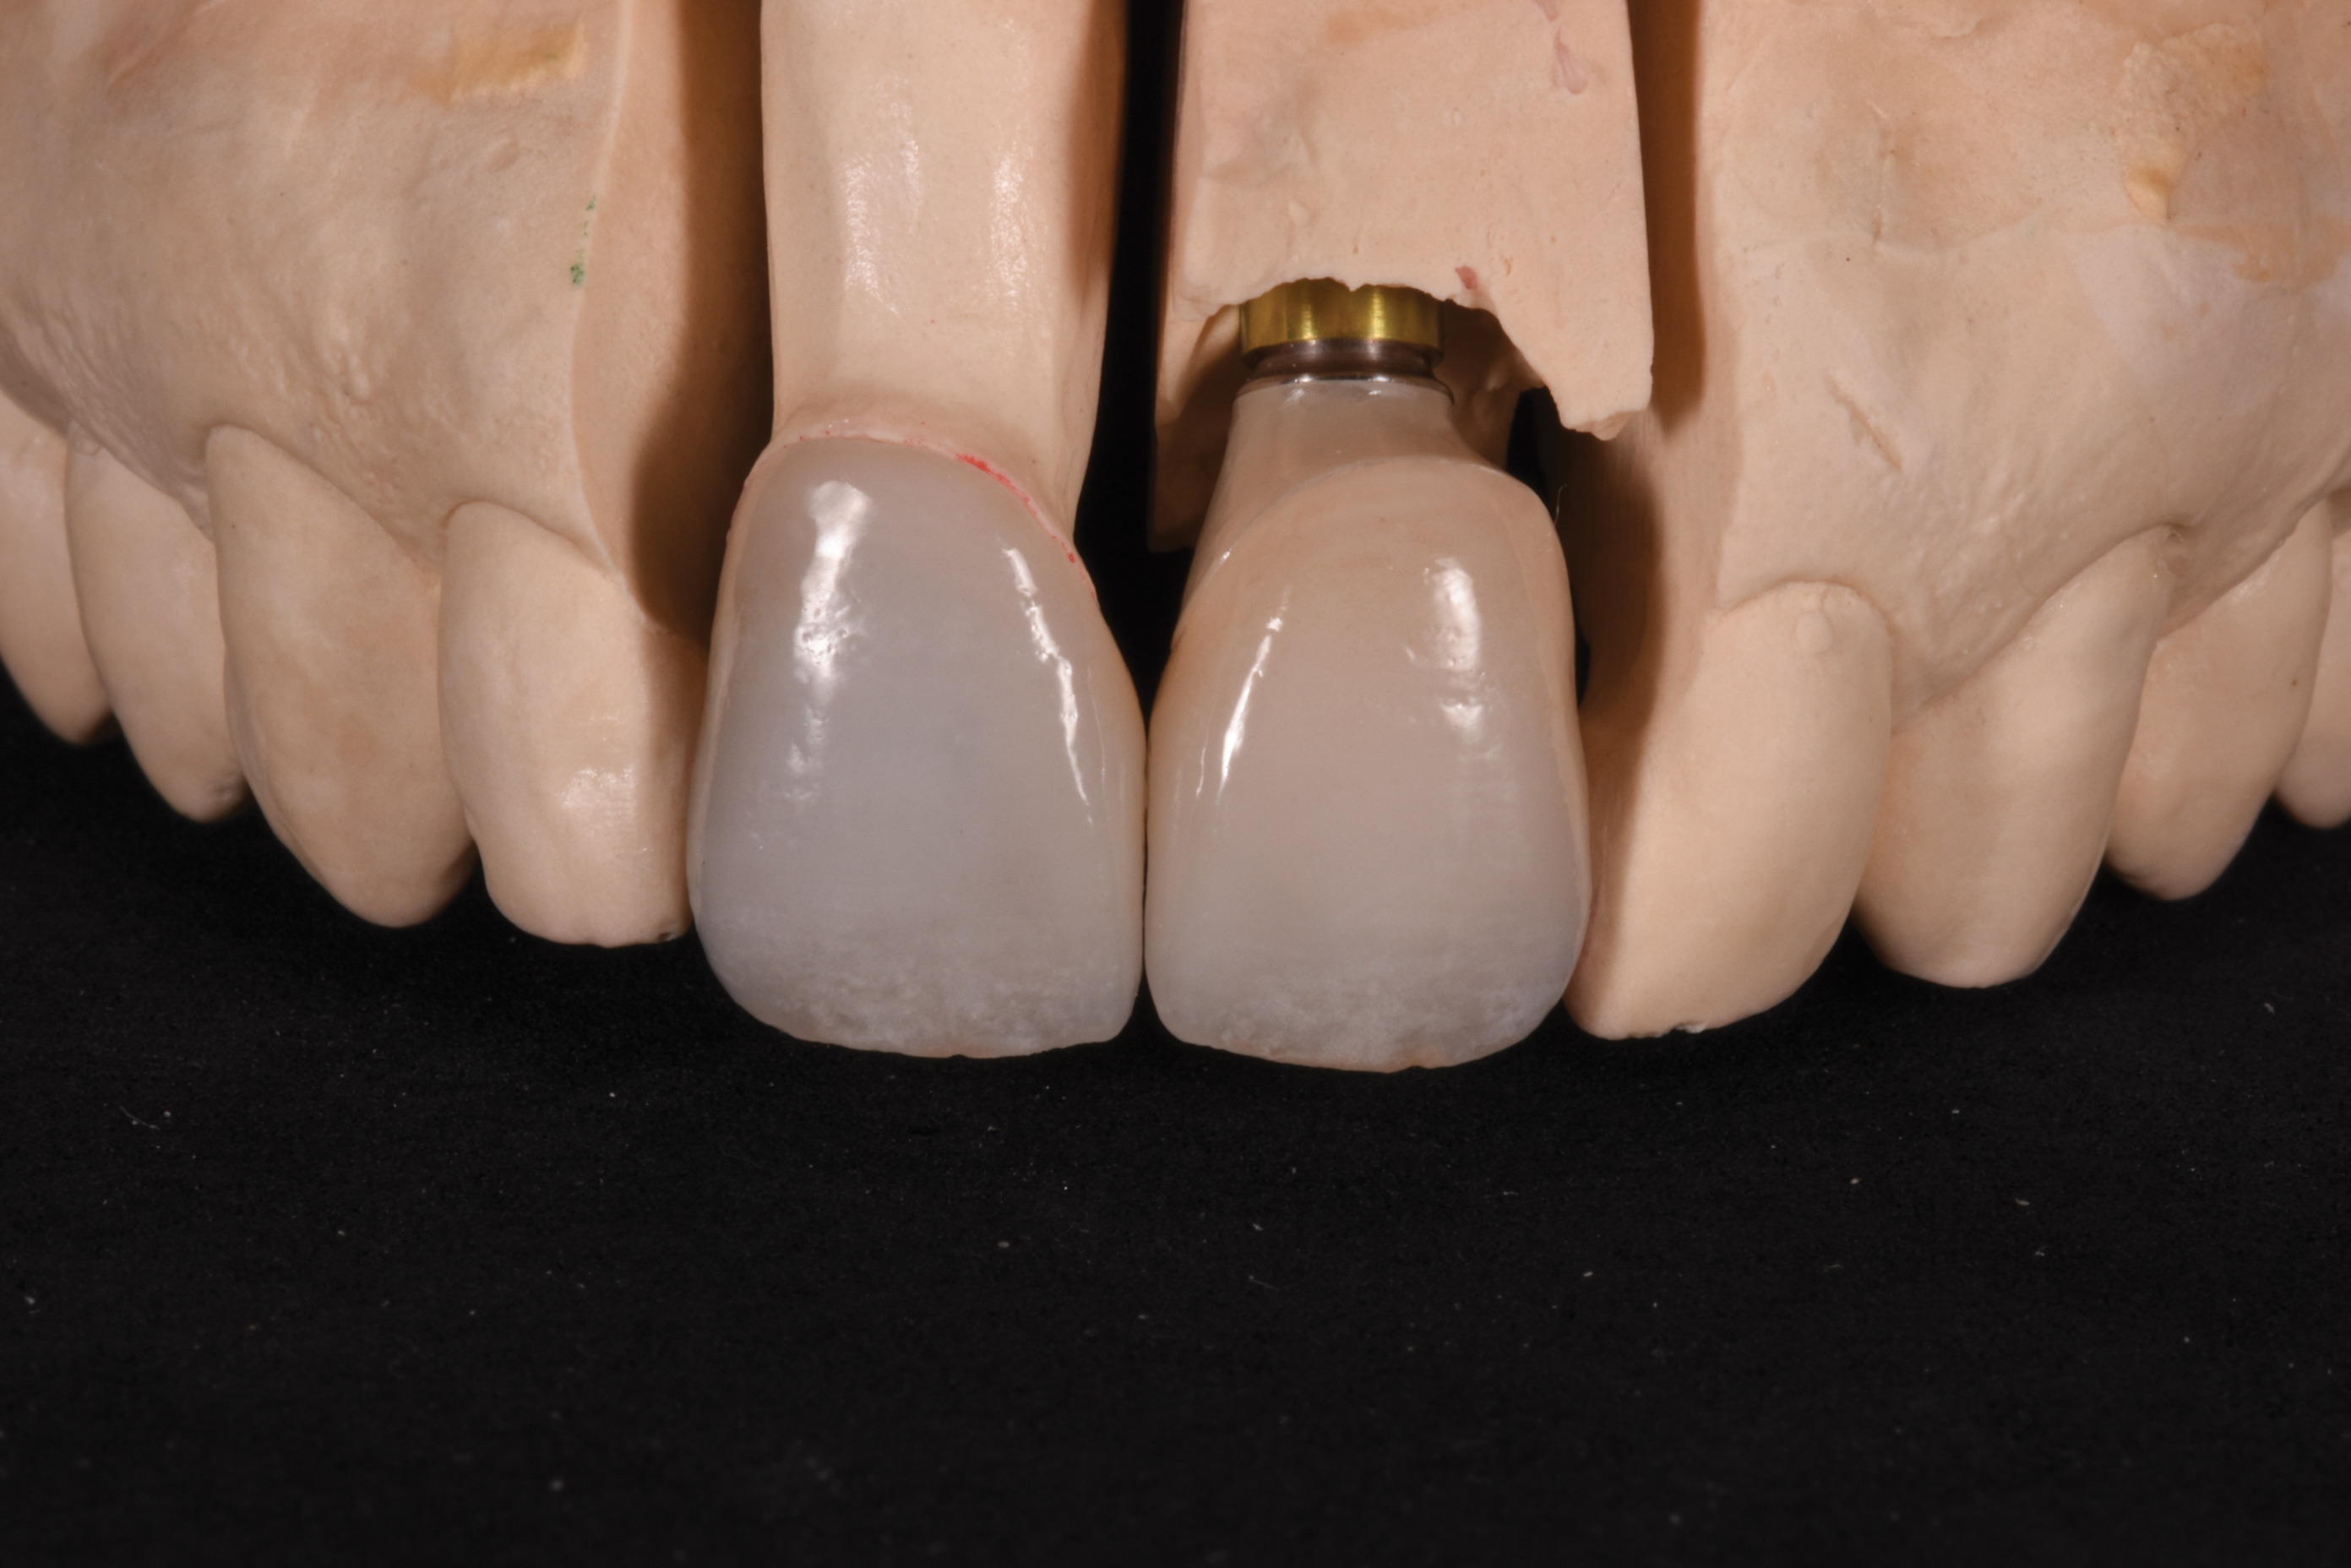

Fig 7. Labial view (laboratory) of wax pattern and copy milled zirconia substructure using angulated screw channel system.

Figure 7

Fig 9. Palatal view (laboratory) of implant-retained crown with access opening ideally positioned in cingulum due to use of the angulated screw channel system.

Figure 9